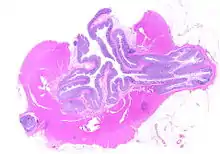

Segmental colitis associated with diverticulosis (SCAD) is a condition characterized by localized inflammation of the colon between diverticula (interdiverticular mucosa) while sparing the diverticular orifices. SCAD may lead to abdominal pain, especially in the left lower quadrant, intermittent rectal bleeding, and chronic diarrhea.